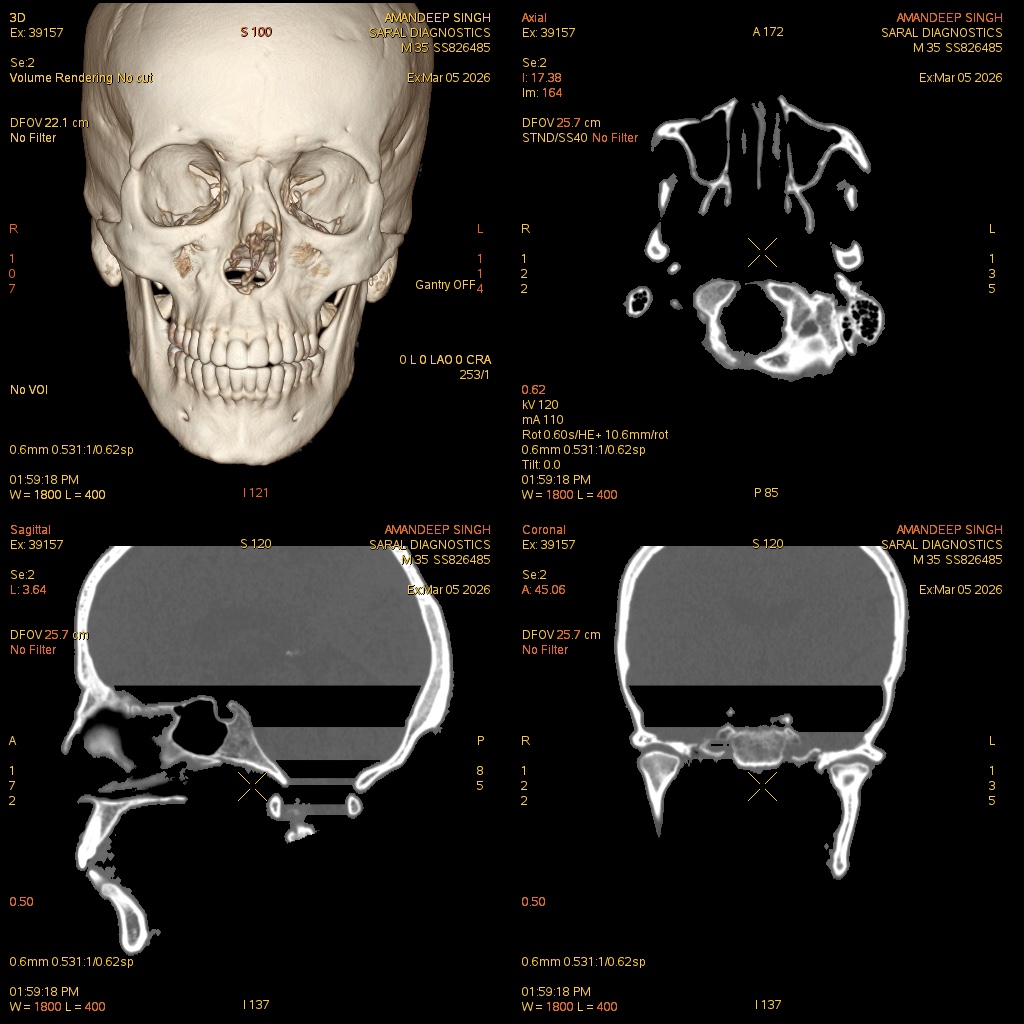

Reference Image

Face Contrast

The Face Contrast CT scan is a high-resolution imaging procedure that evaluates the facial bones, sinuses, soft tissues, and vascular structures using intravenous contrast. The contrast enhances visibility of blood vessels, tumors, infections, fractures, and inflammatory or vascular abnormalities. It is indicated for patients with facial trauma, chronic sinusitis, tumors, vascular lesions, or pre-surgical planning. The scan provides detailed 3D and cross-sectional images, allowing clinicians to assess anatomical relationships accurately, plan interventions, and monitor treatment outcomes. Non-invasive and fast, it helps detect subtle soft tissue changes, enhances diagnostic accuracy, and supports precise surgical or therapeutic decision-making. The procedure minimizes discomfort while offering comprehensive evaluation of facial anatomy, bones, and vascular structures.